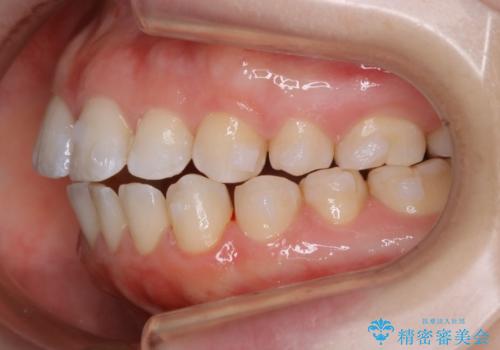

【非抜歯】上下の前歯が噛み合わないオープンバイトの治療

- 噛み合わせの不調を主訴にご来院されました。

骨格的な問題もあり、噛んだ時に奥歯しか当たらず前歯の被蓋があまりない状態でした。

奥歯を沈めて噛み込みを深くしていくことで被害の改善が起こるとともに、下顎自体が前上方に回転移動することで顔貌的にも変化を出すことができます。

臼歯の位置が高く噛んだ時に奥歯しか当たらなかったり、舌癖などが原因で前歯が前に倒れてしまうことで上下の前歯の被蓋がなくなってしまっている状態をオープンバイトといいます。

前者の場合は臼歯を圧下し沈めてあげることで改善させます。後者の場合は前方に傾斜している歯を元の角度に戻してあげることで改善しますが、舌癖がある場合はその癖自体を無くす治療をしない限りまた同じ状態へと後戻りしてしまいます。